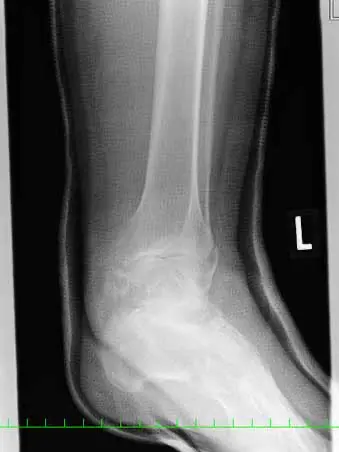

(図5)術後X線像

脛骨内果はcancellus screw2本、腓骨外果は1/3円プレート、脛骨天蓋部は骨欠損部にオスフェリオンを充填し、cancellus screw2本にて固定している。踵骨裂離骨片はスパイクワッシャー付cancellus screwにて固定し、Leeds-Keio人工靭帯にて補強している。